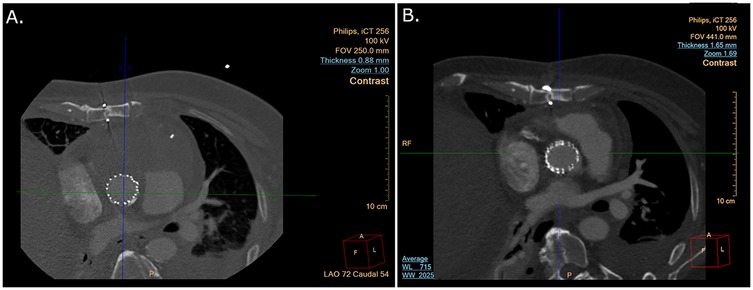

The patient was immediately transferred to the catheterization laboratory. Access to the left femoral artery with an 8-F introducer for stent delivery and to the right femoral vein with a 6-F introducer for a temporary pacemaker was achieved under ultrasound guidance. Left radial access was used to place a pigtail catheter in the sinotubular junction (STJ). The procedure was performed under transesophageal echocardiography (TEE) imaging, which revealed a pseudoaneurysm with a mixed echo-dense and liquid content (Figures 2A,B and Supplementary Video S1) compressing the left atrium, resulting in a restrictive filling pattern.

Figure 2

Two transesophageal echocardiogram images. Image A shows blood flow dynamics with color Doppler indicating red and blue areas, suggesting different flow directions. Image B shows a greyscale cardiac structure without color Doppler. Both images include ultrasound settings and heart rate; Image A shows 72 bpm and Image B shows 66 bpm.

Figure 2. (A) Blood flow into the pseudoaneurysm opening by TEE. (B) Liquid and solid content on TEE.